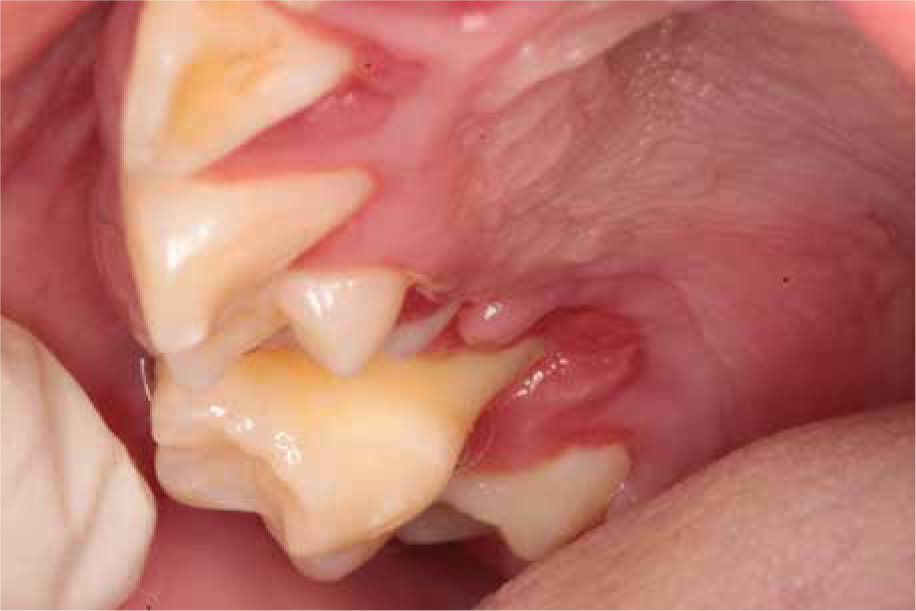

The next year, tartar deposits in the incisors of the mandible and gingivitis were discovered, and the mandibular first molars and central incisors showed signs of second-degree loosening. The patient was recommended to continue conservative treatment and undergo removal of the tartar deposits under antibiotic treatment (amoxicillin with clavulanic acid, 2 doses of 30 mg/kg with an interval of 12 hours, given at home). A few months later (Fig. 5), examination revealed intensified inflammation around tooth 36 with its roots halfway exposed, as well as looseness of teeth 32-42. Extraction of tooth 36 was performed under local anesthesia in an outpatient setting and covered with intravenous antibiotic (amoxicillin with clavulanic acid 30 mg/kg/dose).